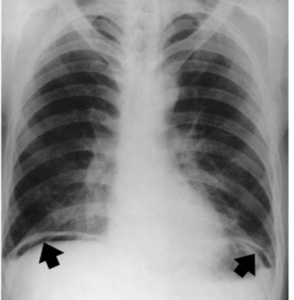

Imaging: X-ray erect abdomen with lower lobes may show free air under the diaphragm (pneumoperitoneum), while a CT scan provides more detailed information about the location of perforation and can comment on surrounding structures.